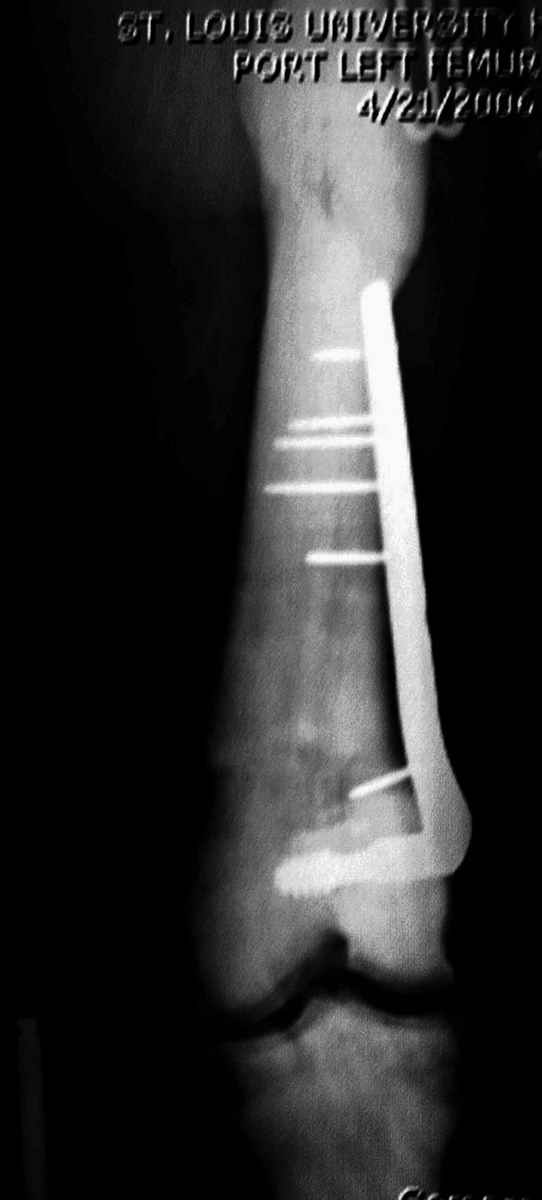

Для примера привожу случай из архива американской ассоциации рентгенологов (ACR) - развитие злокачественной фиброзной гистиоцитомы на левой б.берцовой кости у пациента с множественными инфарктами костного мозга (рис 4,5 - левая, рис 6 - правая)

Не являюсь специалистом по костной патологии, но мне кажется, на ренгенограмме множественные мета-диафизарные образования напоминяющее змееподобных извилистых линии и периостеальные ламинирование очень напоминяет картину остеонекроза (инфаркта) костей, возможно связано с длительным применением стероидов.

При предоставлении дополнительных информации, сканнирования, МРТ и лабараторных данных можно уточнить предварительный диагноз, пока склонен к обширному костному инфаркту, и таких больных рекомендуем лечить сиптоматически.

слайды из прошлегодного случая.